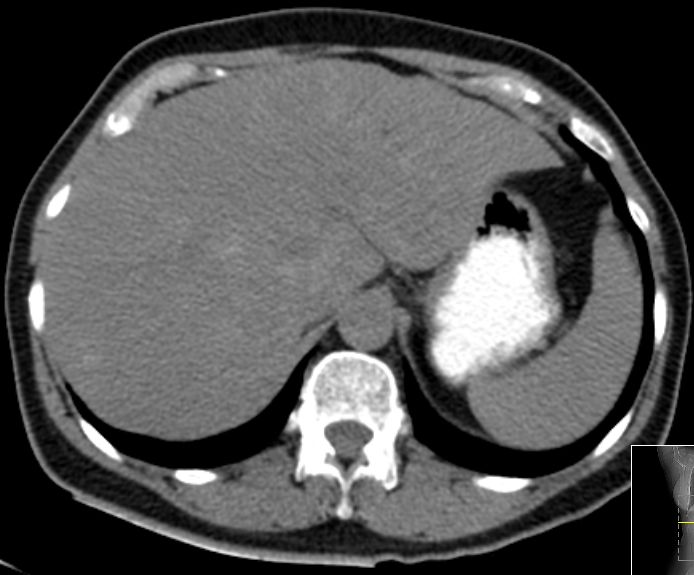

| CT | 75-jähriger Mann, der vor einem Jahr ein Rektum-Karzinom hatte: ypT3a ypN1b(2/18) Mo Li Vo G2. 5x5Gy.

Anteriore Rektumresektion, 4x 5-FU. Jetzt Lebermetastasen.

![]() |